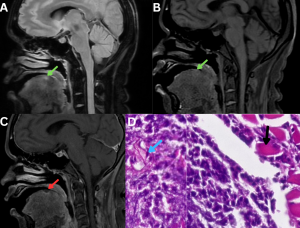

Fig 8: Clinical history:

A 55-year-old diabetic male presented with severe occipital headache, dysphagia, and left-sided otalgia.

Figure A:

Axial CT image of the skull base demonstrates ill-defined soft-tissue density involving the left petrous apex with anterior extension toward the posterior pharyngeal wall (white arrows).

Figure B:

CT bone window image demonstrates erosive changes of the left petrous apex (green arrow). Associated soft-tissue attenuation is noted within the left mastoid air cells (red arrow), likely reflecting eustachian tube obstruction.

Figure C:

Axial contrast-enhanced CT (CECT) image demonstrates heterogeneously enhancing soft tissue involving the left petrous apex with extension into the posterior pharyngeal wall (orange arrows).

Figure D:

Histopathology demonstrates necrotic tissue (black arrow) containing broad, pauci-septate fungal hyphae (blue arrow), consistent with mucormycosis.